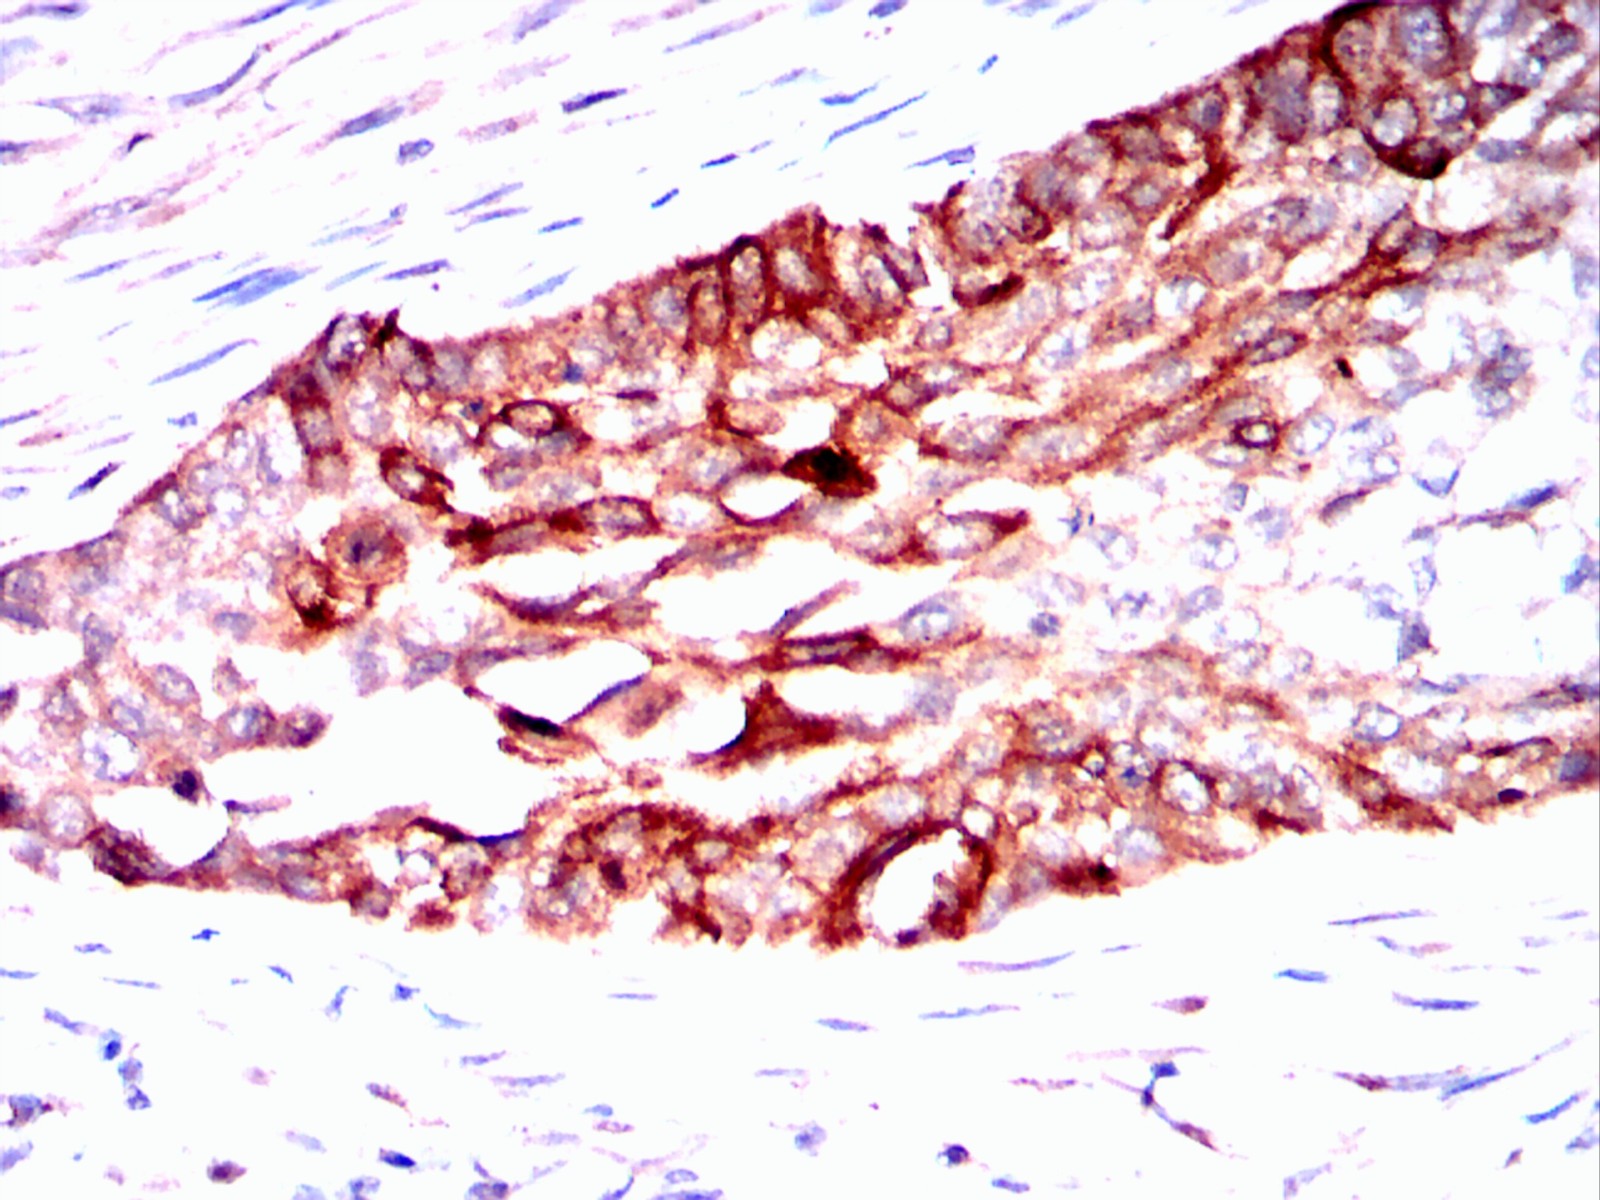

Immunohistochemical analysis of paraffin-embedded esophageal cancer tissues using ERBB3 mouse mAb with DAB staining.

Immunohistochemical analysis of paraffin-embedded esophagus tissues using mouse mAb with DAB staining.